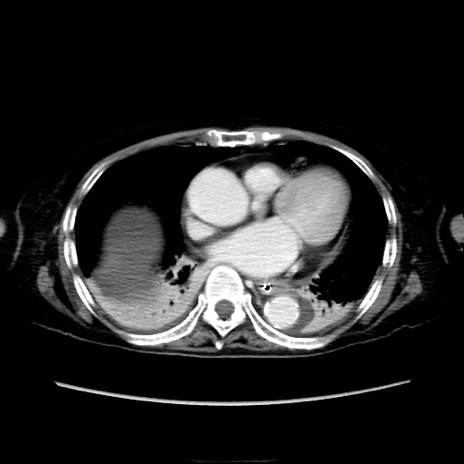

矢状断像